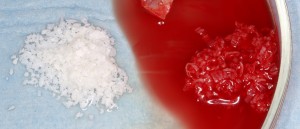

Никакие биоматериалы, никакая «искусственная костная ткань» не содержит в себе живых клеток. Любые биоматериалы следует рассматривать как матрикс, своего рода наполнитель для собственных клеток. Именно поэтому при проведении остеопластики в биоматериалы вводятся клетки костной ткани, как правило в виде стружки:

Таким образом, мы получаем жизнеспособный графт, который легко регенерирует и интегрируется в нужной области. Как в примере (изначальная клиническая ситуация: существенная утрата объема альвеолярного гребня. Необходимы остеопластика и синуслифтинг):

Фрагмент такой сложной конфигурации проще всего выстроить с помощью аутокостной стружки и биоматериала. Тем более, синуслифтинг нужен, а это значит, необходим достаточно большой объем графта. Мы «разбавляем» аутокостную стружку биоматериалом Bio-Oss в пропорции, примерно, 50/50: